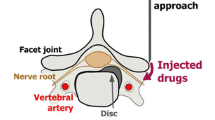

The technique of MR fluoroscopy-guided nerve root infiltration therapy has been described in detail by Streitparth et al. [13]. In brief, the patient was placed in a lateral position, and a multipurpose loop coil was fixed to the back in an orthogonal position to B0, resulting in a maximum signal yield. An interactive PD-w fast spin echo (FSE) sequence (TR/TE 600/10 ms, FOV 200 × 157 mm, matrix 224 × 72 mm, SL 5 mm, TA 2) was used for localising the target anatomy and subsequent multiplanar real-time needle guidance. Two millilitres of Xylonest 1 % (lidocaine and 1 % adrenaline, AstraZeneca, Wedel, Germany) were subcutaneously administered for local anaesthesia. An MR-compatible 20-G needle (MReye™, Cook, Bloomington, IN, USA) was inserted at the predefined dorsolateral entry point. In proximity to the nerve root, the needle position was controlled once more and adjusted in its directionality, if necessary (Fig. 1). After aspiration, a solution of 1 ml Triam (40 mg/ml; triamcinolone acetonide; Winthrop, Fürstenfeldbruck, Germany) and 2 ml Carbostesin 0.5 % (bupivacaine; AstraZeneca, Wedel, Germany) was injected into the periradicular space. A heavily T2-weighted fat-saturated SPIR (Spectral Presaturation with Inversion Recovery) sequence (TR/TE 1,500/100 ms, FOV 200 × 200 mm, NOS 6, matrix 224 × 216 mm, TF 24, SL 3 mm, TA 4.16 s) was acquired to monitor the correct injectant distribution as a means of interventional control. Procedures were defined as technically successful if the injectant was monitored in the perineural sheath of the targeted spinal nerve. The patients were discharged after the puncture site was bandaged with a patch and 30 min of post-interventional monitoring if no increase in pain or discomfort occurred. Interventions were performed by two radiologists with experience of at least 2 years for MR-guided nerve root infiltrations.

Before the intervention, patients were positioned prone on the CT table for pre-interventional scout imaging of the lumbar spine. A metal wire was placed on the skin parallel to the spine on the side of the symptoms to facilitate exact localisation of the target nerve root and to plan the access path on individual CT slices. Finally, the desired puncture site was marked on the skin. The area was covered with sterile drapes, and skin disinfectant was applied, followed by application of superficial local anaesthesia (Xylonest 1 %, AstraZeneca, Wedel, Germany). Under CT fluoroscopy guidance, a 20-G puncture needle (Becton Dickinson SA, S. Agustin del Gualdix, Spain) was advanced until the tip reached the posterior edge of the neuroforamen of the target nerve root (Fig. 2). Following removal of the trocar, a mixture of 2 ml Carbostesin (0.5 %) and 1 ml iodine-based contrast medium (Accupaqe 240, GE Healthcare, Munich, Germany) was administered to document the correct periradicular contrast medium distribution. Finally, 1 ml with 40 mg of triamcinolone acetonide (Winthrop Arzneimittel, Mühlheim, Germany) was administered. Correct positioning of the needle close to the nerve root and adequate periradicular distribution of contrast medium were classified as a technical success. The dose-length product (in mGy*cm) was documented for all patients to calculate approximate effective radiation doses (in millisievert, mSV) using the software CT-expo version 2.0.1. Interventions were performed by three different radiologists with at least 1 year of experience in CT-guided nerve root infiltrations.